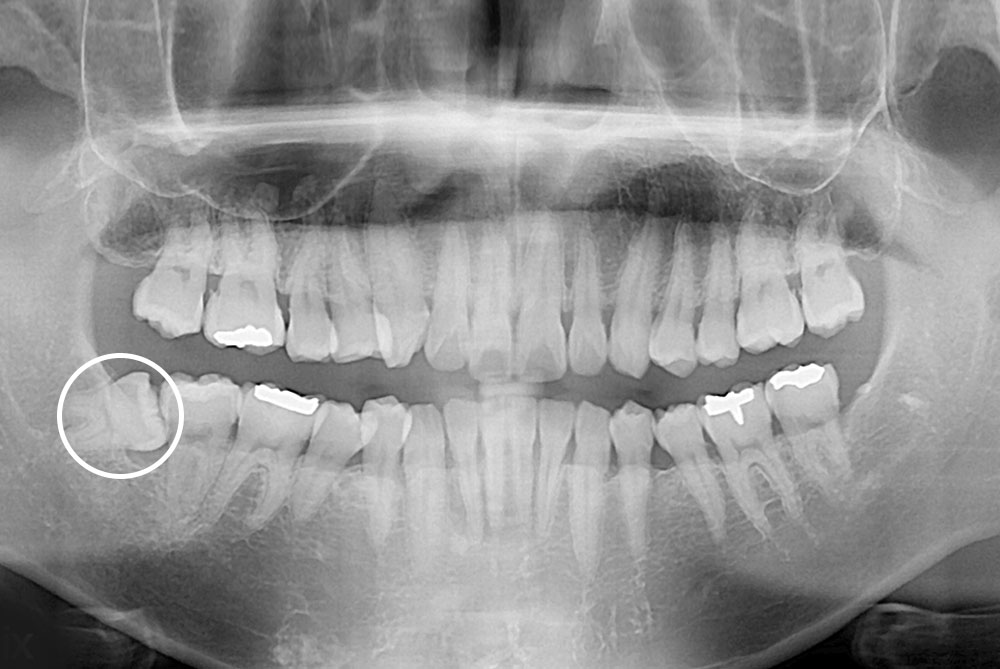

[사랑니] 매복 사랑니 발치

치료후 : 2021-12-31

세종치과는 구강악안면외과학 박사이신 원장님이 발치하는 치과입니다.